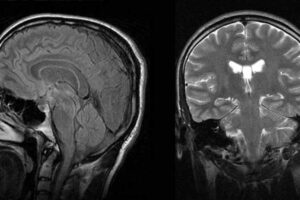

NARCOLEPSY BRAIN AND NORMAL BRAIN